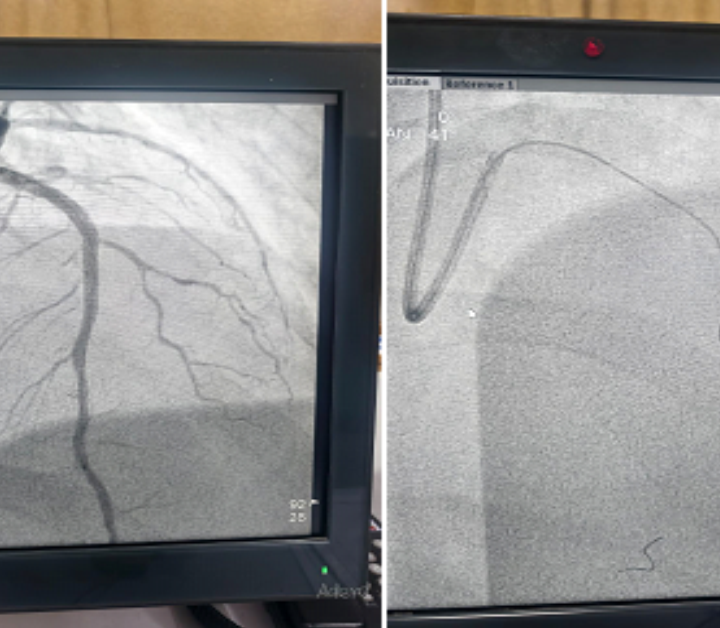

I wanted to share one interesting case… life-saving procedure done in our Cath lab, Cardiology department…

Happy to share, one interesting complex case, which was done in our Cardiology department cath lab last week.